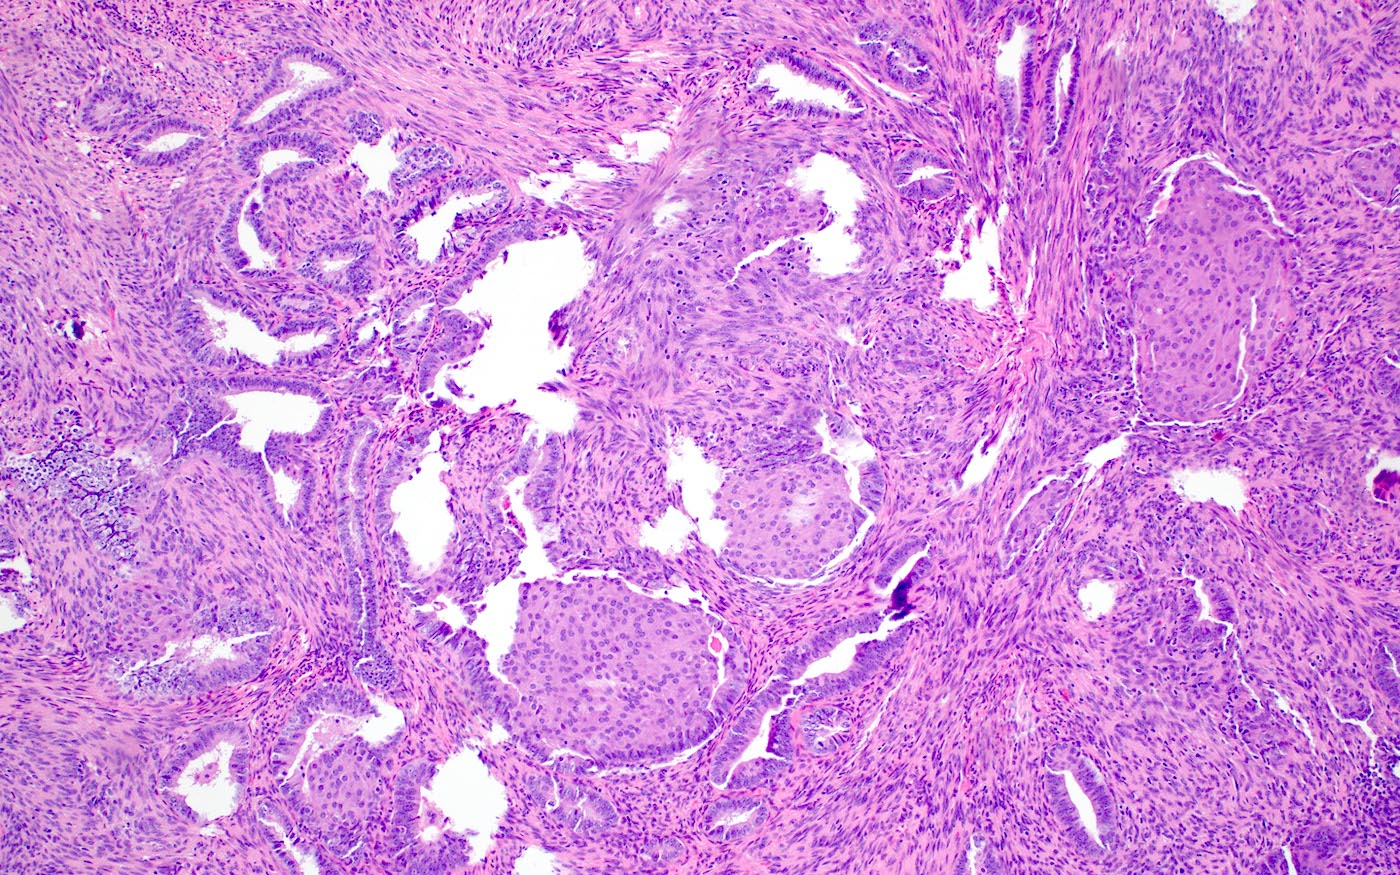

Microscopic (histologic) description

- Biphasic tumor:

- Endometrioid glands, usually with complex architecture and sometimes with cytologic atypia

- Glandular component often shows lobulated architecture

- Benign fibromyomatous stroma, rarely with myxoid change

- Squamous morular metaplasia is frequently seen and may show central necrosis

- Well circumscribed or slightly irregular margin

- Reference: Am J Surg Pathol 2015;39:1148

Microscopic (histologic) images